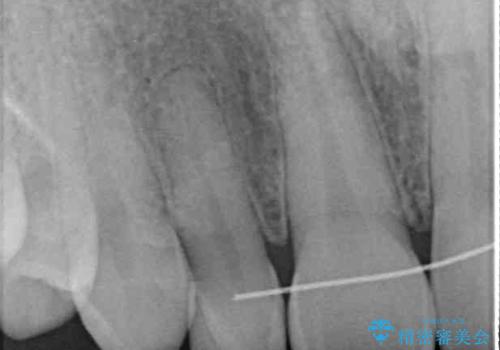

- ラミネートベニアと歯の境目の着色を気にして来院された患者様です。

矯正治療後に矮小歯であった歯をラミネートベニアにて形を変えたそうですが、矯正歯科治療直後であったためか、歯肉の位置が変わったことで境目が見えていました。

着色の原因として、湿気の多い環境で接着操作を行うと、境目に細かいギャップができてしまうことが考えられます。

接着の際にはラバーダムを使用して、乾燥した環境を整えて処置を行いました。